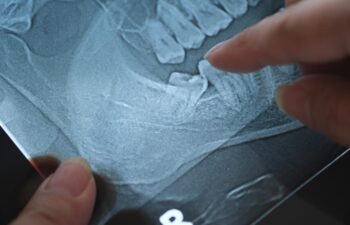

When the wisdom teeth are not able to fully erupt into the mouth and become fully functional teeth that can be properly cleaned and maintained, they need to be extracted. If they are not extracted, they can cause overcrowding in the jaw and can leave spaces for bacteria to form. This can lead to future dental health problems.

A wisdom tooth extraction is a common procedure that takes place in a dental or oral surgery office with the use of some type of anesthesia. For this procedure, a local anesthetic, oral sedative medication or I.V. sedation can be used. In some cases where complications may be expected, a wisdom tooth extraction can take place in a hospital setting under general anesthesia.